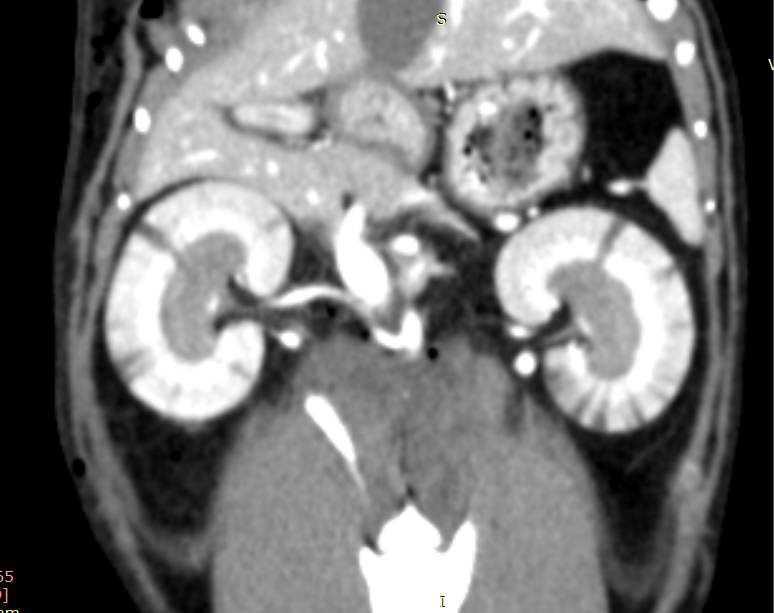

КТ-ангиография – наглядный метод диагностики, который может быть использован для демонстрации расположения тромба. По КТ-ангиографии оценивают дефект заполнения артериального сосуда контрастным веществом (рис. 7).

Помимо расположения самого тромба на КТ, необходимо исследовать другие ткани и органы на наличие дефектов контрастирования. В нашей практике у животных с ТЭК мы обнаруживали мелкие инфаркты коркового слоя почек, которые до этого не удавалось выявить на УЗИ (рис. 8), и сегментарный дефект распределения контраста в паренхиме селезенки.